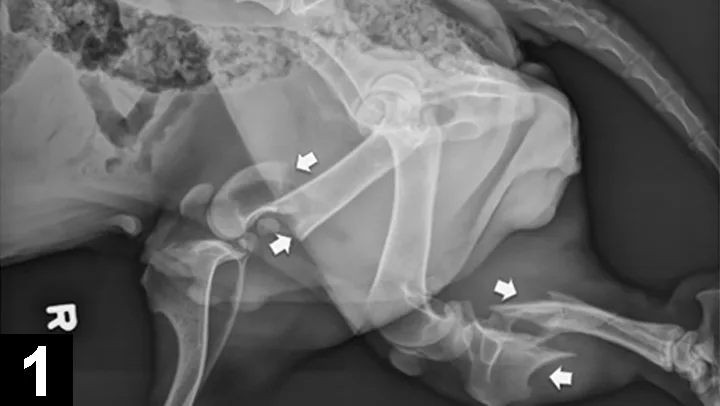

Blunt (eg, vehicular) trauma patients often experience multiple injuries (Figure 1). Patients are often only treated for the obvious fracture, causing additional traumatized tissues or disease processes to go unnoticed and untreated. Signs may not show for hours or days, which could alter the outcome of the treatment plan.3 Common additional injuries (affecting 25%–50% of blunt trauma patients) include:

Figure 1

Lateral radiograph of an adult basset hound presented for inability to walk on its hind legs, without evidence of superficial abrasions or bruises. The arrows mark a distal femoral fracture and a proximal tibial fracture.